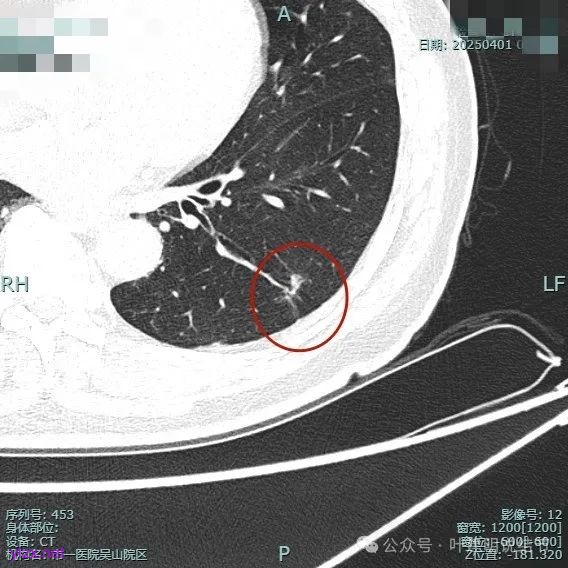

再看2025年4月初复查的情况:

整体纵向仍偏长条些,实性部分不太致密,边上磨玻璃成分的轮廓与界限不太清楚,毛刺显得长。

仍有支气管扩张,但较2024年时密度感觉低了点。

密度较淡且缺乏收缩力。

密度杂乱,血管进入,但血管说不上明显异常增粗,磨玻璃成分淡而瘤肺界限欠清。

总体较之前密度有减低,缺乏聚拢性。